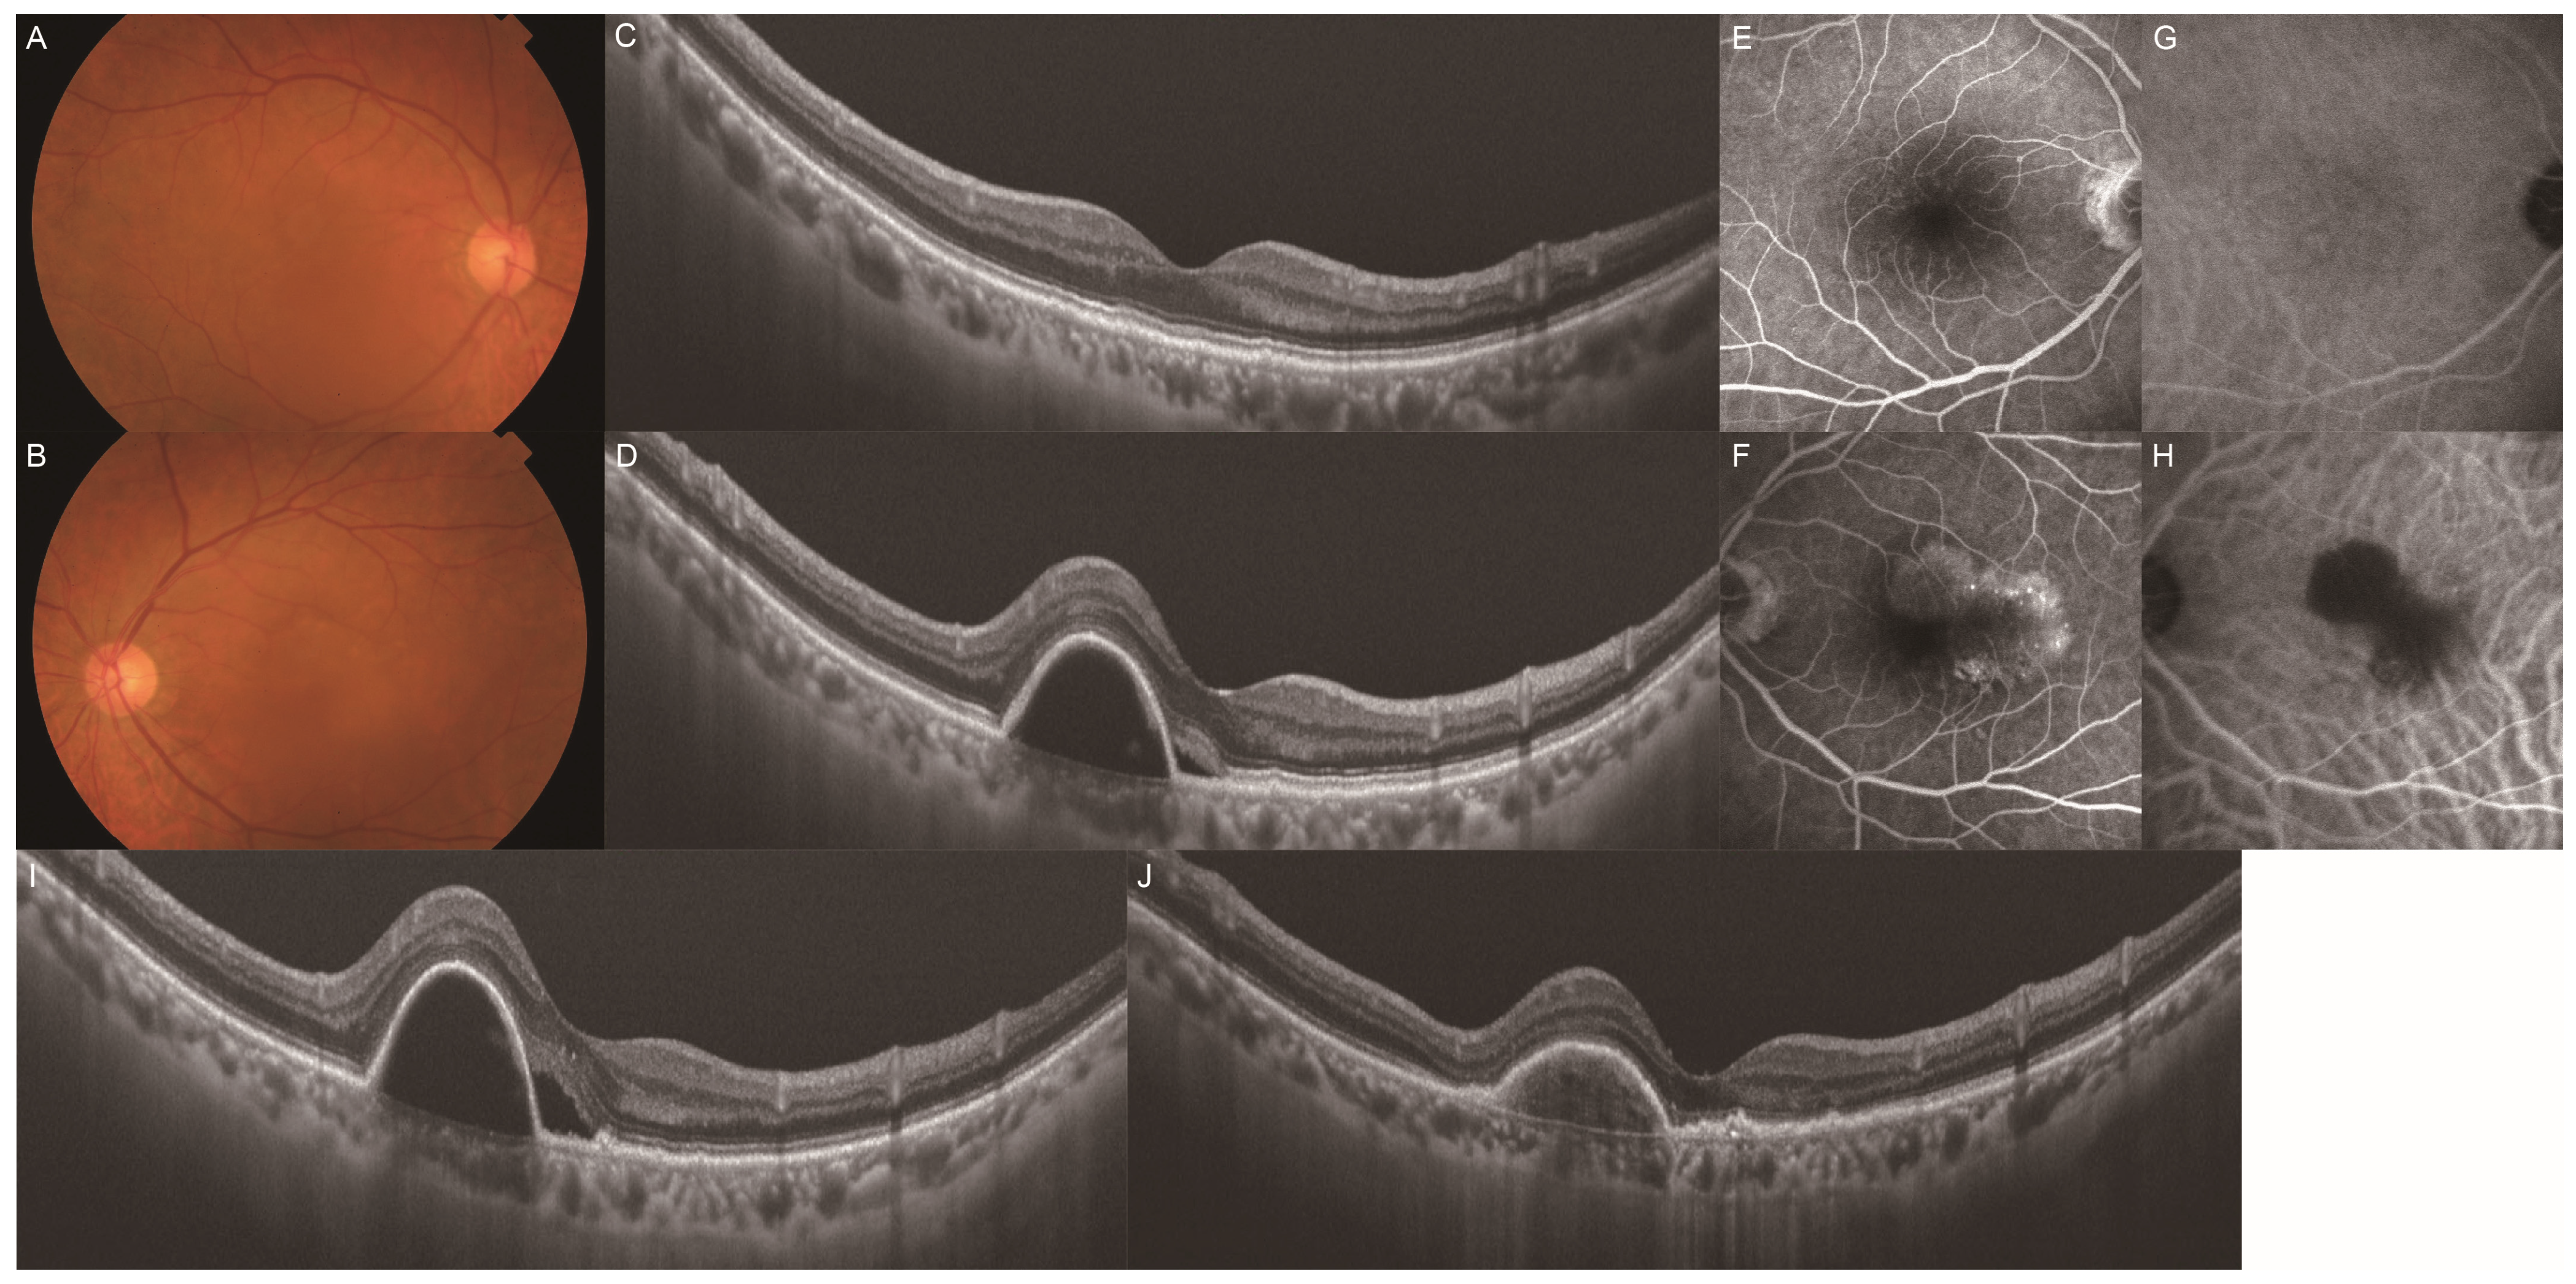

Clinical Characteristics of Punctate Hyperfluorescence Spots in the Fellow Eye of Patients with Unilateral Macular Neovascularization with No Drusen

- Tsujikawa, A.; Ojima, Y.; Yamashiro, K.; Ooto, S.; Tamura, H.; Nakagawa, S.; Yoshimura, N. Punctate hyperfluorescent spots associated with central serous chorioretinopathy as seen on indocyanine green angiography. Retina 2010, 30, 801–809. [Google Scholar] [CrossRef] [PubMed]

- Park, S.J.; Kim, B.H.; Park, K.H.; Woo, S.J. Punctate hyperfluorescence spot as a common choroidopathy of central serous chorioretinopathy and polypoidal choroidal vasculopathy. Am. J. Ophthalmol. 2014, 158, 1155–1163. [Google Scholar] [CrossRef] [PubMed]

- Kim, H.; Lee, J.H.; Kwon, K.Y.; Byeon, S.H.; Lee, S.C.; Lee, C.S. Punctate hyperfluorescent spots associated with polypoidal choroidal vasculopathy on indocyanine green angiography. Ophthalmic. Surg. Lasers Imaging Retina. 2015, 46, 423–427. [Google Scholar] [CrossRef]

- Kang, H.G.; Han, J.Y.; Kim, M.; Byeon, S.H.; Kim, S.S.; Koh, H.J.; Lee, C.S. Pachydrusen, choroidal vascular hyperpermeability, and punctate hyperfluorescent spots. Graefes Arch. Clin. Exp. Ophthalmol. 2021, 259, 2391–2400. [Google Scholar] [CrossRef]